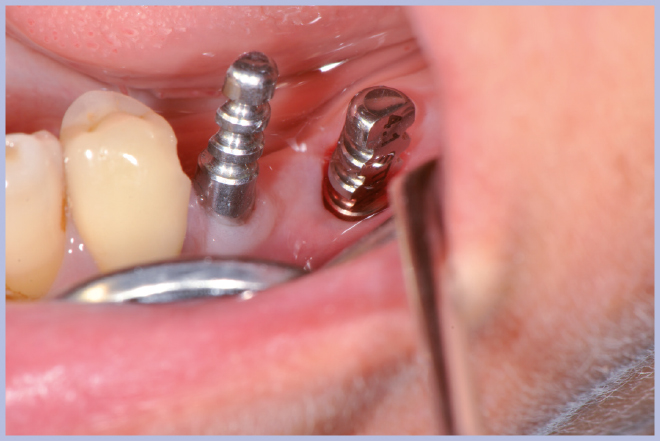

Viene quindi richiesto al tecnico di modificare in laboratorio la mascherina radiologica mediante il posizionamento delle boccole di guida adatte agli impianti da posizionare (Exacone® 6.5 e Exacone® 3,3×8) in asse con gli analoghi del modello Master 3D ed eliminando il repere radiologico standardizzato, trasformandola così nella dima chirurgica (Figg. 14, 15). Si procede quindi alla prova della mascherina sulla paziente per verificarne la stabilità e la corrispondenza esatta con il modello Master 3D (Fig. 16). La seduta chirurgica con tecnica flapless, guida chirurgica e Frese Zero1 dedicate non presenta alcuna difficoltà ; al termine dell’inserimento si posizionano sugli impianti tappi di guarigione bassi per permettere loro di guarire con tecnica sommersa (Figg. 17-27). Si effettua nella stessa seduta una CBCT che dimostra che la posizione clinica degli impianti risulta sovrapponibile a quella progettata dagli Autori (Figg. 28-30).

- Fig. 21 – Cambio carrier impianto per posizionamento guidato

- Fig. 22 – Posizionamento impianto Exacone® Ø 3,3 con tappo basso

- Figg. 23-27 – Procedura guidata per inserimento impianto corto Exacone® 6.5